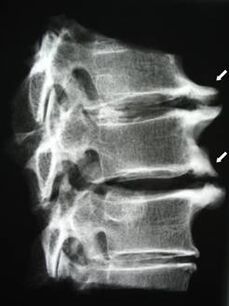

Nos estágios iniciais, a osteocondrose é detectada por ressonância magnética. Mais tarde, a patologia pode ser diagnosticada por meio de radiografia. Nas radiografias da coluna cervical, tornam-se perceptíveis diminuição da distância entre as vértebras, alterações patológicas nas articulações facetárias e osteofitose.